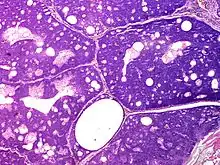

Sebaceoma (also known as a "sebaceous epithelioma") is a cutaneous condition that appears as a yellow or orange papule.[1]: 662